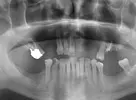

Implant tedavisi

Çene Kistleri